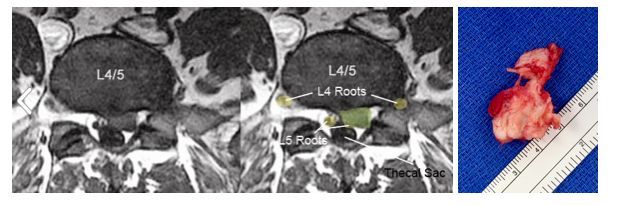

This is why we need to understand anatomy 👇

6️⃣ Stages of spinal degeneration in 1️⃣ MRI.

A 🧵... Image

This lady presented with worsening low back pain with radiation of pain into both legs with walking (neurogenic claudication)

Her MRI shows signs of a typical cascade of spinal degeneration at a single level (L4/5) as follows.... Image

Image

1. L4/5 Spondylolisthesis (Grade 1) Image